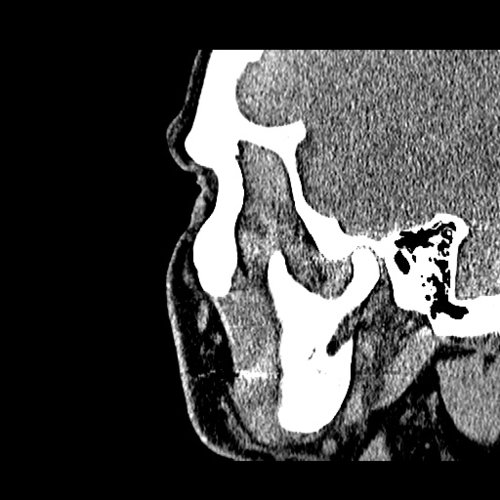

From www.embodi3d.com

Chronic sinusitis Dental, Orthodontic, Maxillofacial CTs Orthodontic Sinusitis Odontogenic sinusitis (ods) can present a therapeutic dilemma because multiple treatment strategies have been reported. Ods is distinct from rhinosinusitis in that it is. Sinusitis is an inflammation of the mucosal lining of the paranasal sinuses. It is actually inflammation of the maxillary sinus. Learn about the potential impact of orthodontic treatment on sinus issues, tips for preventing complications, and. Orthodontic Sinusitis.